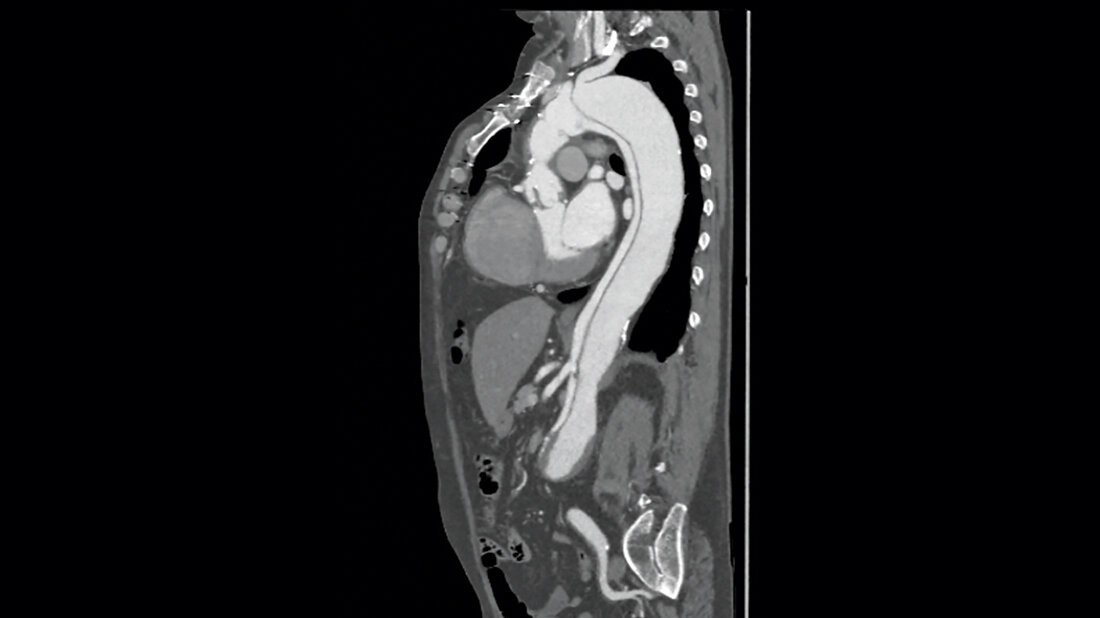

Die Falldarstellung zeigt den Erkrankungsverlauf eines 49-jährigen Patienten mit Typ-B-Aortendissektion. Relevante Vorerkrankungen und Risikofaktoren sind eine arterielle Hypertonie sowie eine Übergewichtigkeit und ein Nikotinabusus.

Schlüsselwörter: Aortendissektion, Typ-B-Aortendissektion, CT, Aortenstentprothese